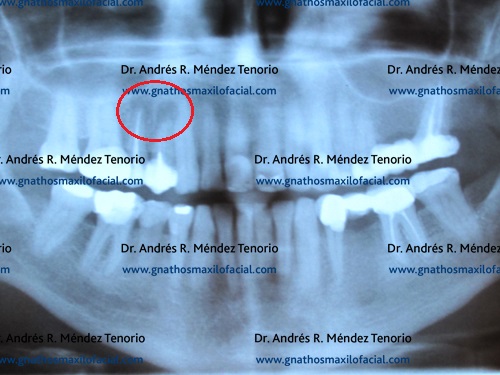

| Rx panorámica donde se observa resto radicular de premolar superior derecho junto a una lesión periapical del premolar adyacente | |